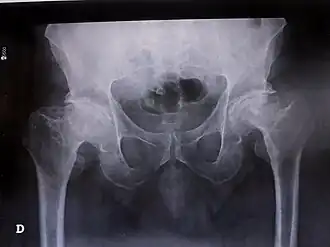

| Síndrome de Legg-Calvé-Perthes num adulto do sexo masculino com 52 anos (radiografia) | |